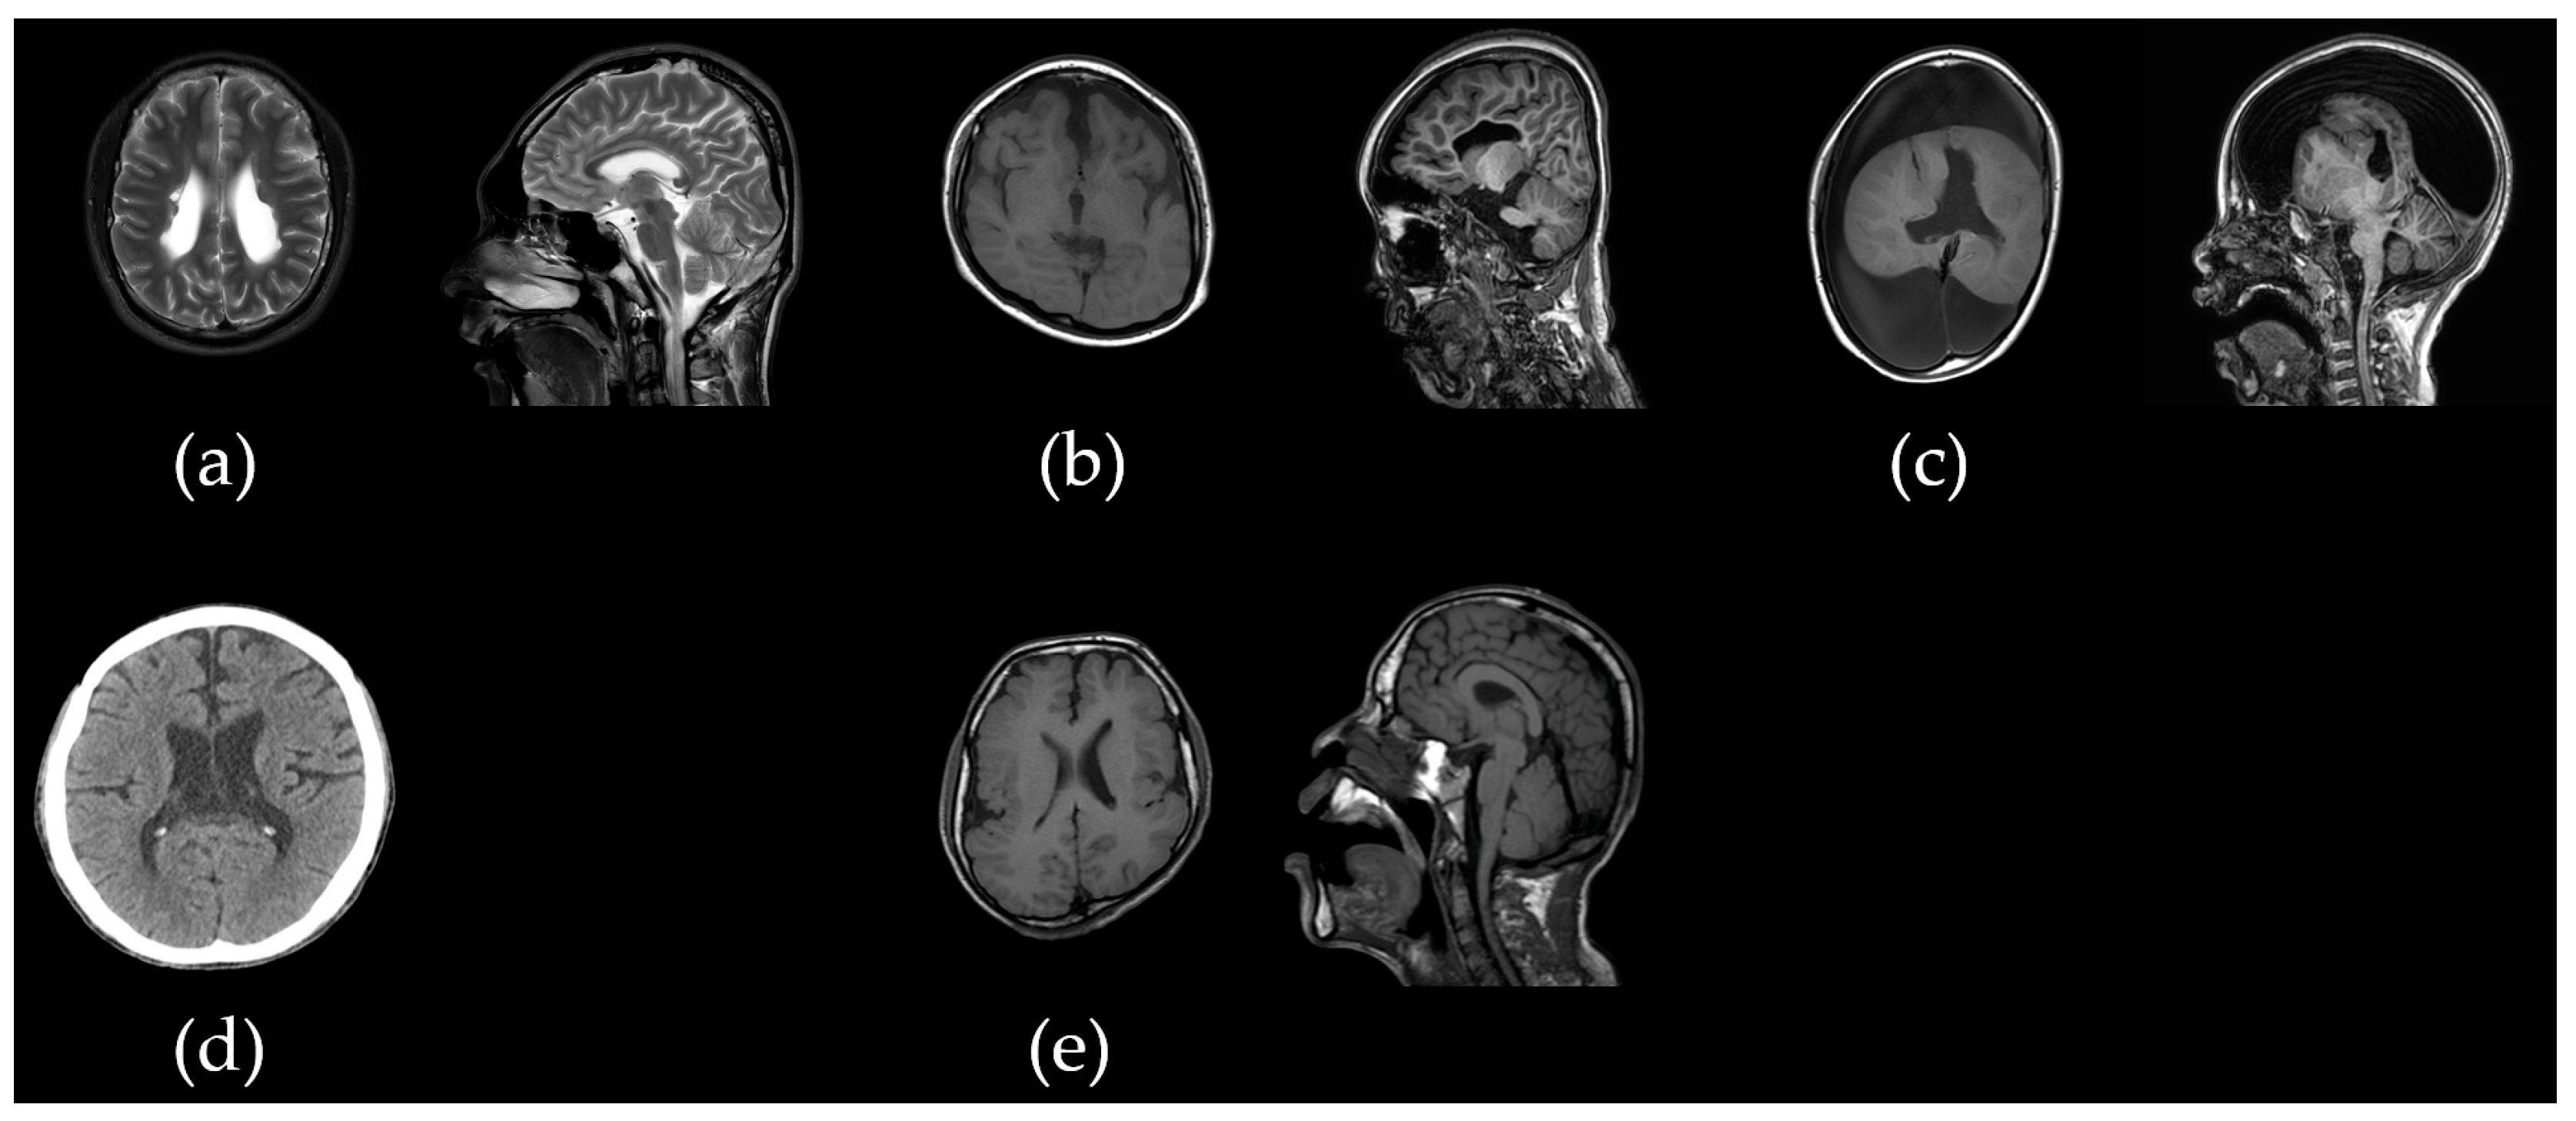

2.1.1. Patient acp01k with SLC2A1 c.277C>T/p.Arg93Trp Variant

2.1.3. Patient acp03k with Bi-Allelic PLAA c.1039+1G>A and c.1834C>T/p.Pro612Ser Variants

2.1.4. Patient acp05y with CDC42BPB c.4049G>A/p.Arg1350Gln Variant

2.1.6. Patient acp07l with CACNA1D c.1846T>C/p.Cys616Arg Variant

2.1.7. Patient acp08p with Bi-Allelic ALG12 c.437G>A/p.Arg146Gln and c.788A>G/p.Tyr263Cys Variants

2.1.8. Patient acp09k with 12p13.33p11.23 Duplication and 18p11.32 Microdeletion

2.1.9. Patient acp10k with Bi-Allelic SACS c.11101T>C/p.Trp3701Arg and c.12973C>T/p.Arg4325Ter Variants